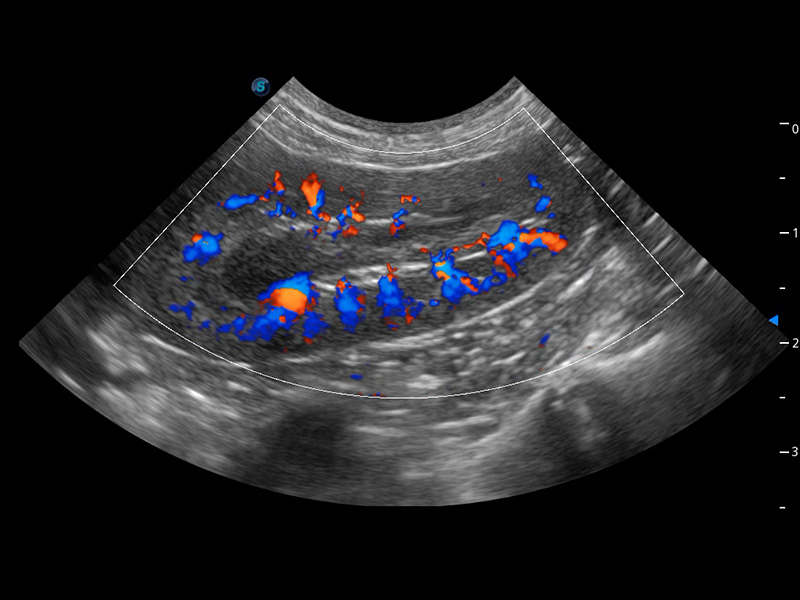

ProPet 60 作为一款高端台式动物超声设备,为动物医生的日常诊断提供了一系列贴合动物临床需求、解决临床实际问题的高级成像功能。凭借全系列高清探头,满足医生对腹部、心脏、生殖、浅表、肌骨等成像的所有需求,切实帮助您提升检查效率,提高诊断信心。

动物是人类最亲密的朋友和最值得信赖的伙伴。云顶集团官网也一直致力于探索动物专用的超声影像解决方案。 全新推出的ProPet系列,是云顶集团官网在动物超声影像智能化、专业化、精准化的一次跨越式革新。动物不能用言语来表述自己的不适,通过超声影像,ProPet系列搭建了动物医生与不同物种沟通的“桥梁”,为动物医生注入了“治愈之力”。